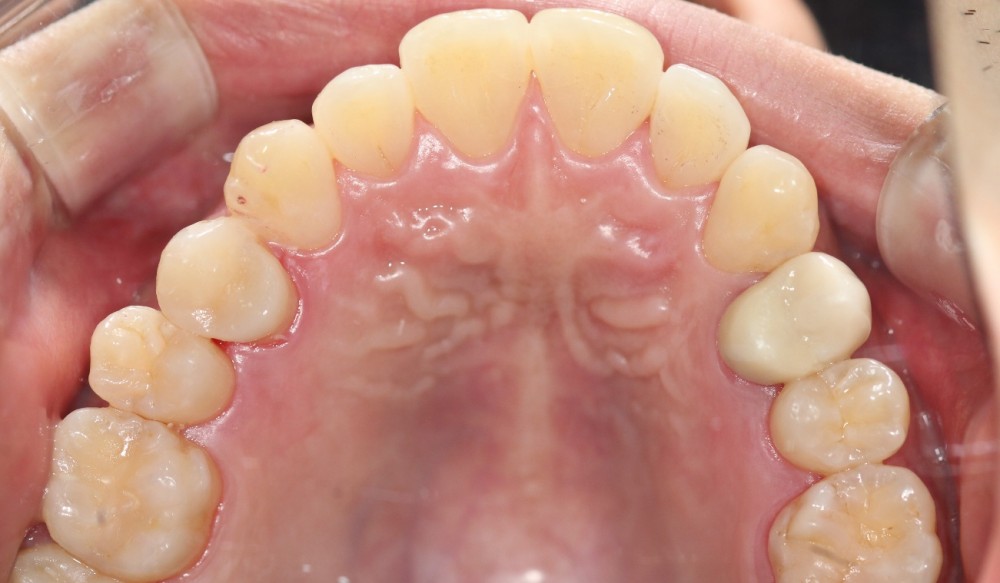

이맥스 인레이로 충치 치료하였습니다.

어느 치아가 치료한 치아일까요?

찾기 어려우시죠?

이처럼 이맥스 인레이는 아주 심미적이면서도 강도도 충분한 좋은 치료방법입니다.